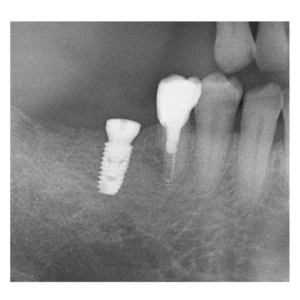

治療途中のインプラント症例

治療途中のインプラント症例です。